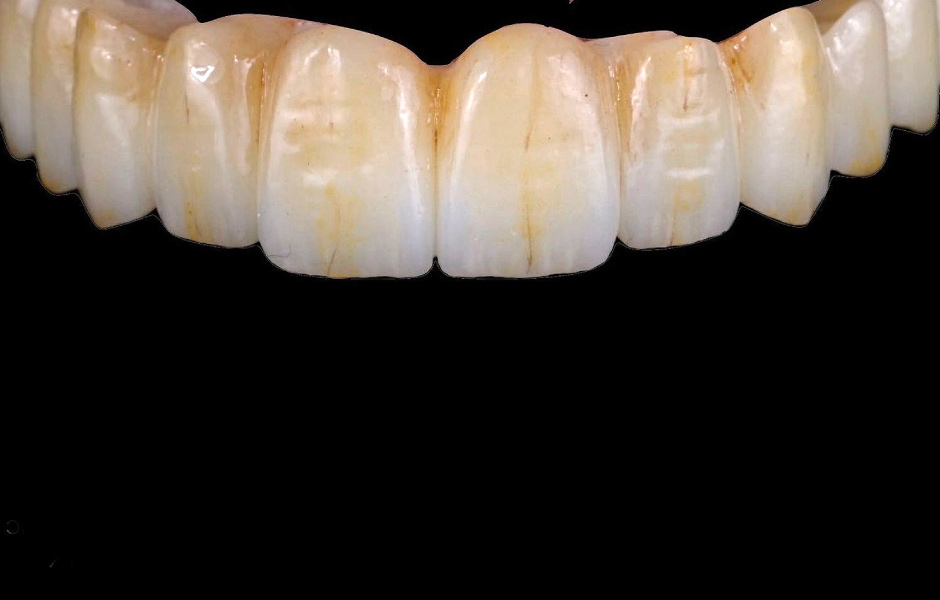

Pro kotvení definitivní náhrady byly použity abutmenty Variobase® for Bridge. Materiálem pro výrobu definitivní náhrady byl zvolen monolitický zirkon (obr. 49, 50).

Definitivní náhrada byla nasazena a ověřena z hlediska estetiky, okluze a funkce (obr. 51–55). Panoramatický kontrolní snímek potvrdil, že všechny parametry protetického ošetření odpovídají očekávaným hodnotám (obr. 56).

Obr. 49

Obr. 50

Obr. 51

Obr. 52